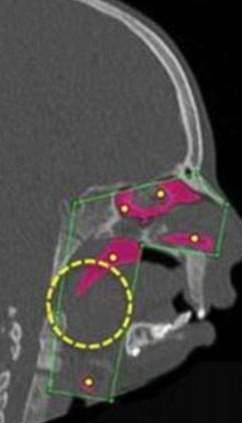

▼他们决定旋转汉娜部分的骨骼,让她的气管能够因此畅通连接,经历一系列的手术并休养后,汉娜终于在近日接受了最重要的气管重建手术,也来到她目标的最后一步。

▼哈波医生成功地执行了这项手术,手术后,汉娜的气管从一开始极为狭窄的状况,终于被扩通!